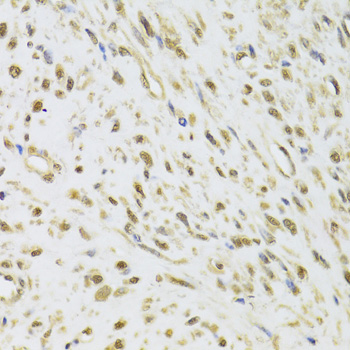

Immunohistochemistry of paraffin-embedded rat brain using DDX1 Antibody.

Immunohistochemistry of paraffin-embedded mouse brain using DDX1 Antibody.

Immunohistochemistry of paraffin-embedded human leiomyoma of uterus using DDX1 Antibody.